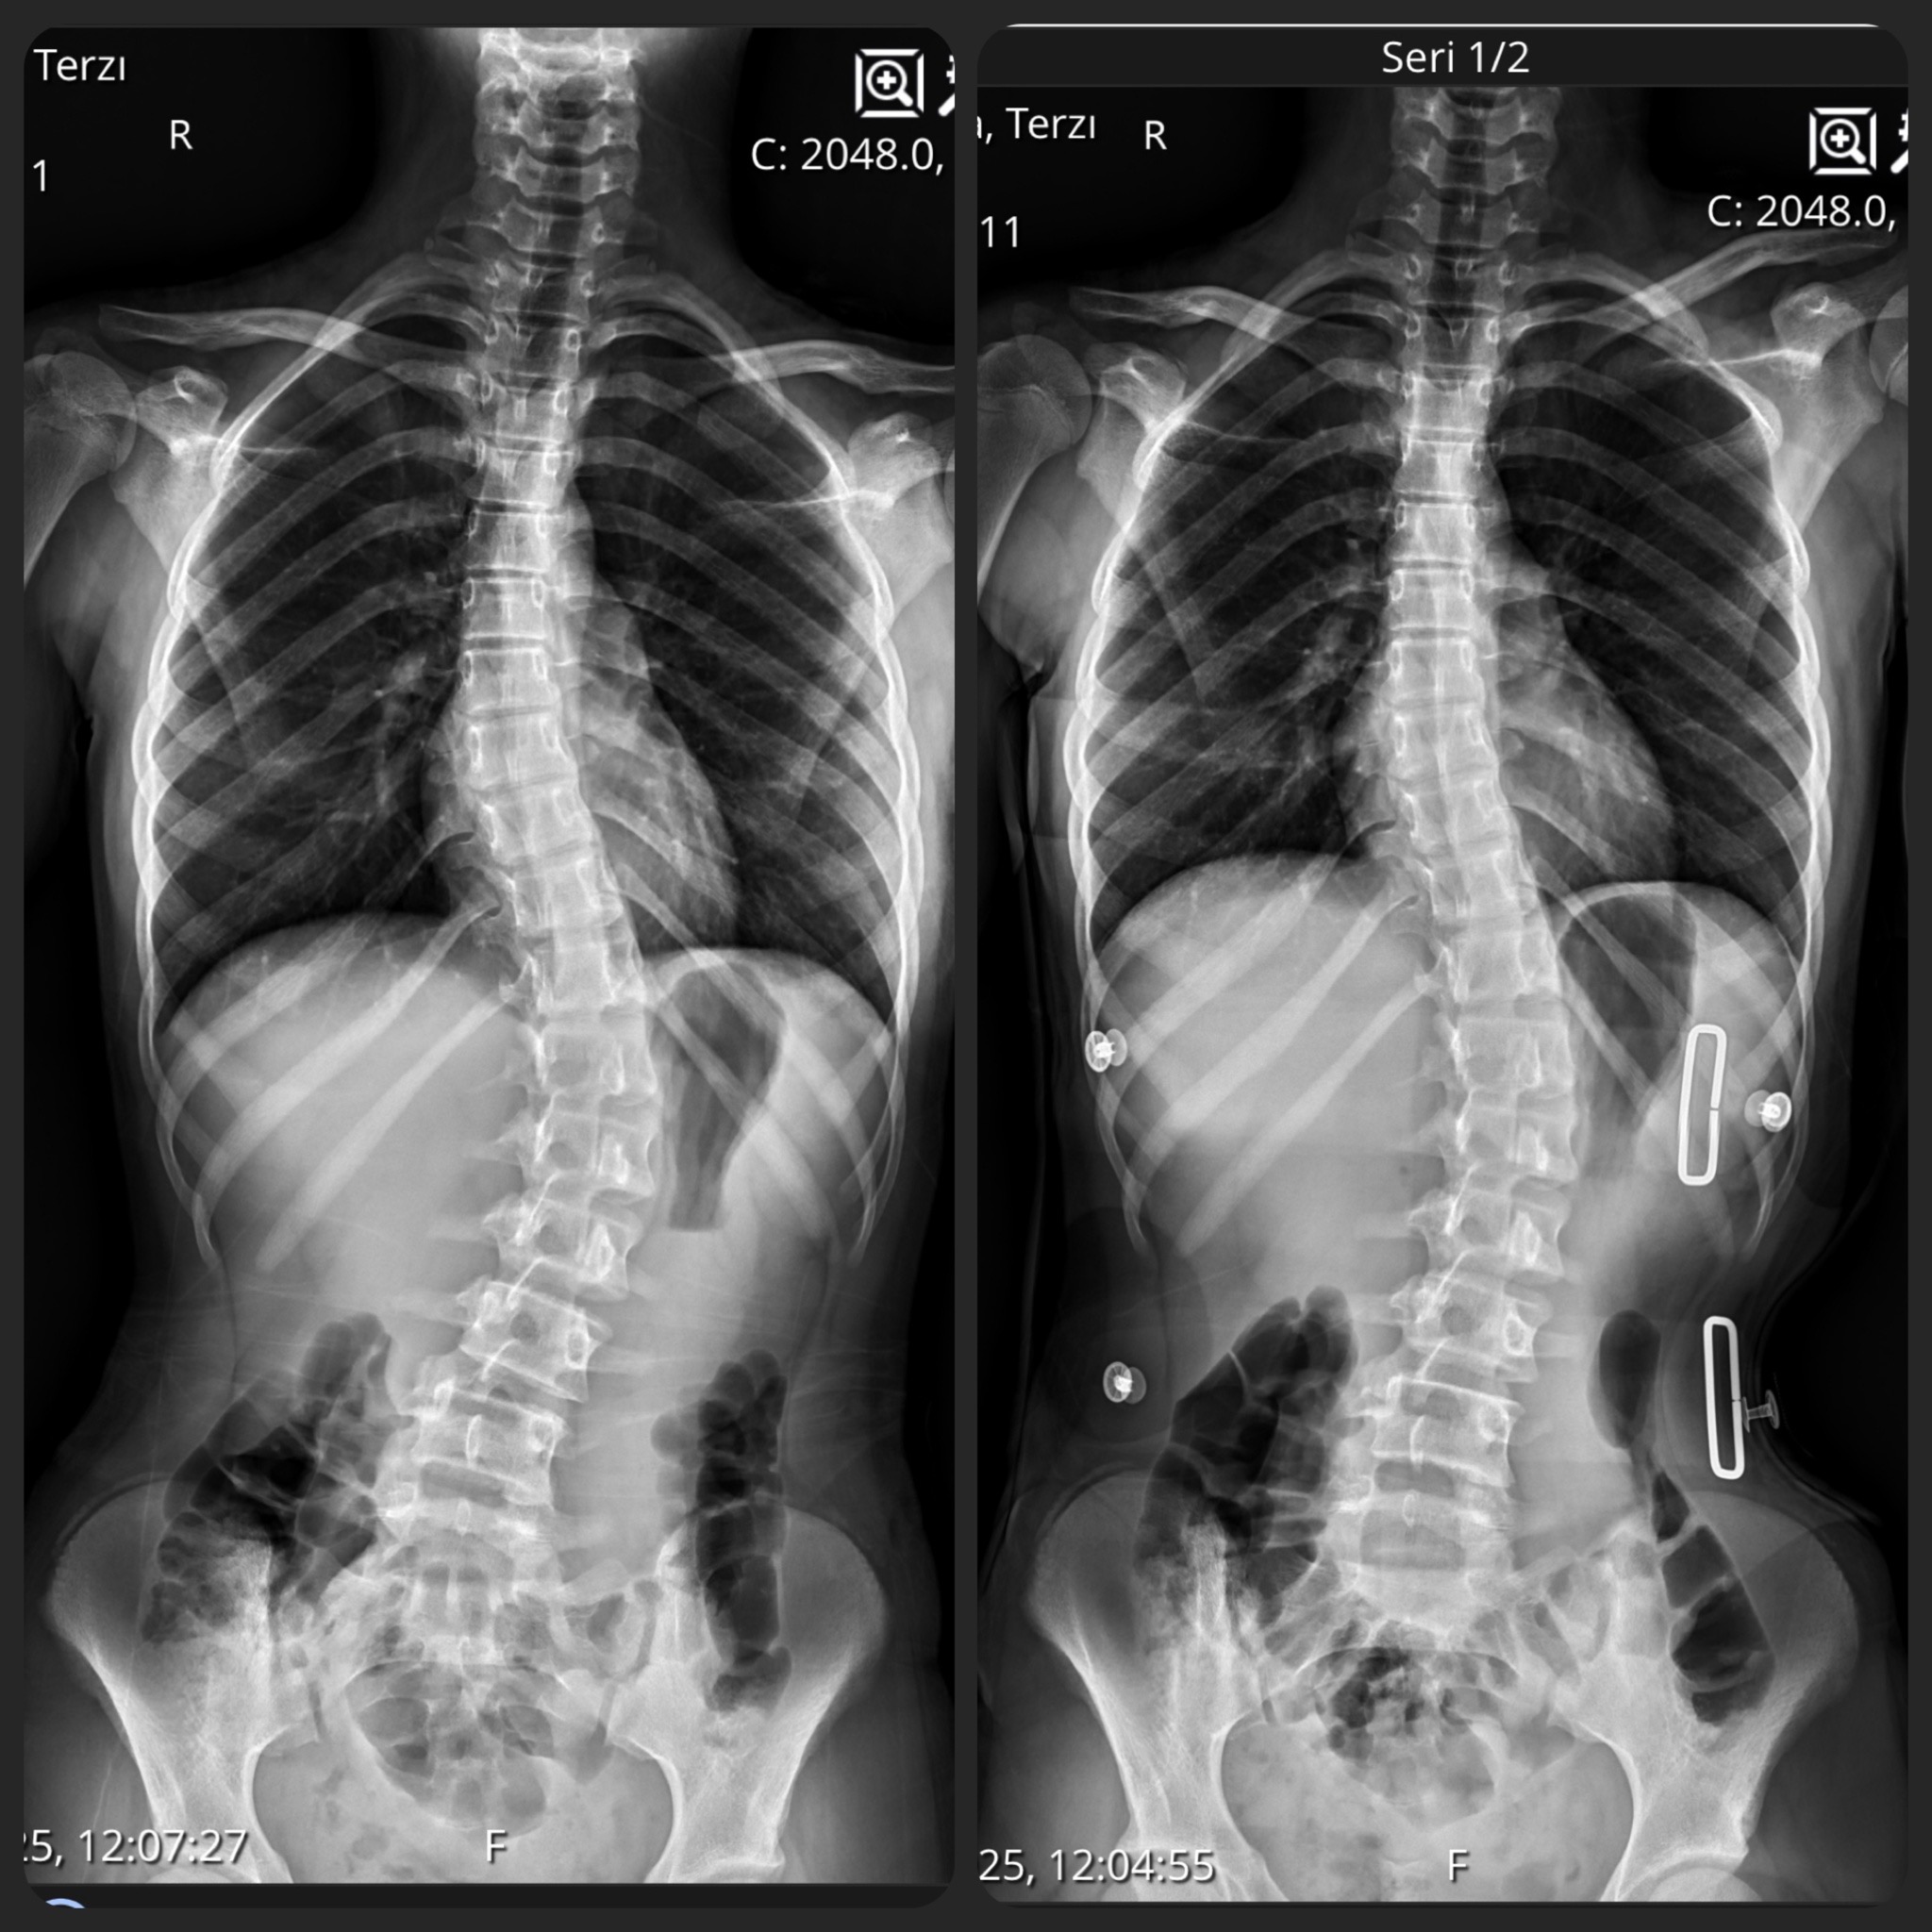

CAD/CAM (Bilgisayar Destekli Tasarım) sistemlerimizle, röntgen üzerindeki eğrilik derecesine (Cobb açısı) tam zıt kuvvet uygulayan, asimetrik Gensingen/Cheneau tipi korseler tasarlıyoruz.

Uyguladığımız 3D korseler ile elde ettiğimiz düzeltme sonuçlarından bazı örnekler.